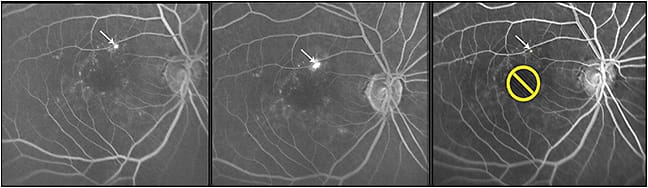

2. Accurate localization: Localization of leakage on FFA and the ability to use this information accurately for treatment are the major advantages of Navilas in CSC (Figure 1). Previous reports have shown that laser photocoagulation using the navigated laser system is safe and achieves a higher rate of accuracy (92%) in photocoagulation than conventional (72%) laser in the treatment of diabetic retinopathy microaneurysms.9 Point leakage in CSC requires accurate laser photocoagulation to achieve successful closure.

Figure 1. Fundus fluorescein angiography images (left panel: midphase; middle panel: late phase) showing point of leak (arrow) in an eye with central serous chorioretinopathy. Right panel shows the laser plan with yellow spot (arrow) on planned laser spot with no-laser zone (yellow circle).